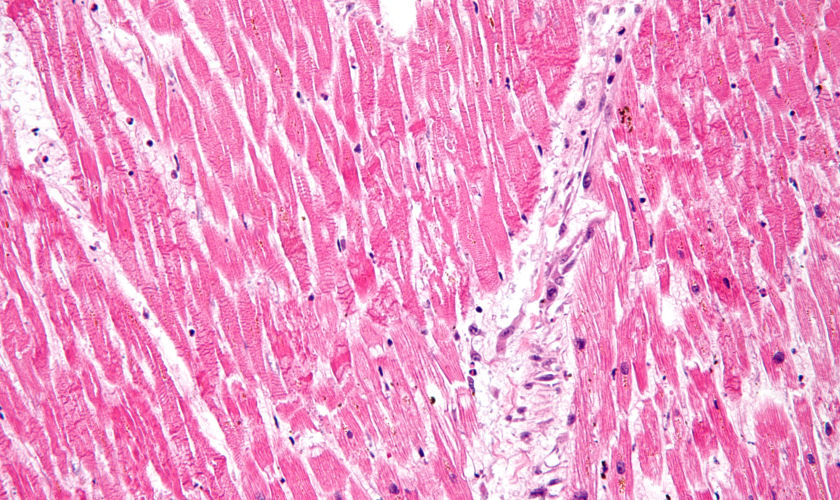

back acute myocardial infarction

Source: MI with contraction bands high mag.jpg